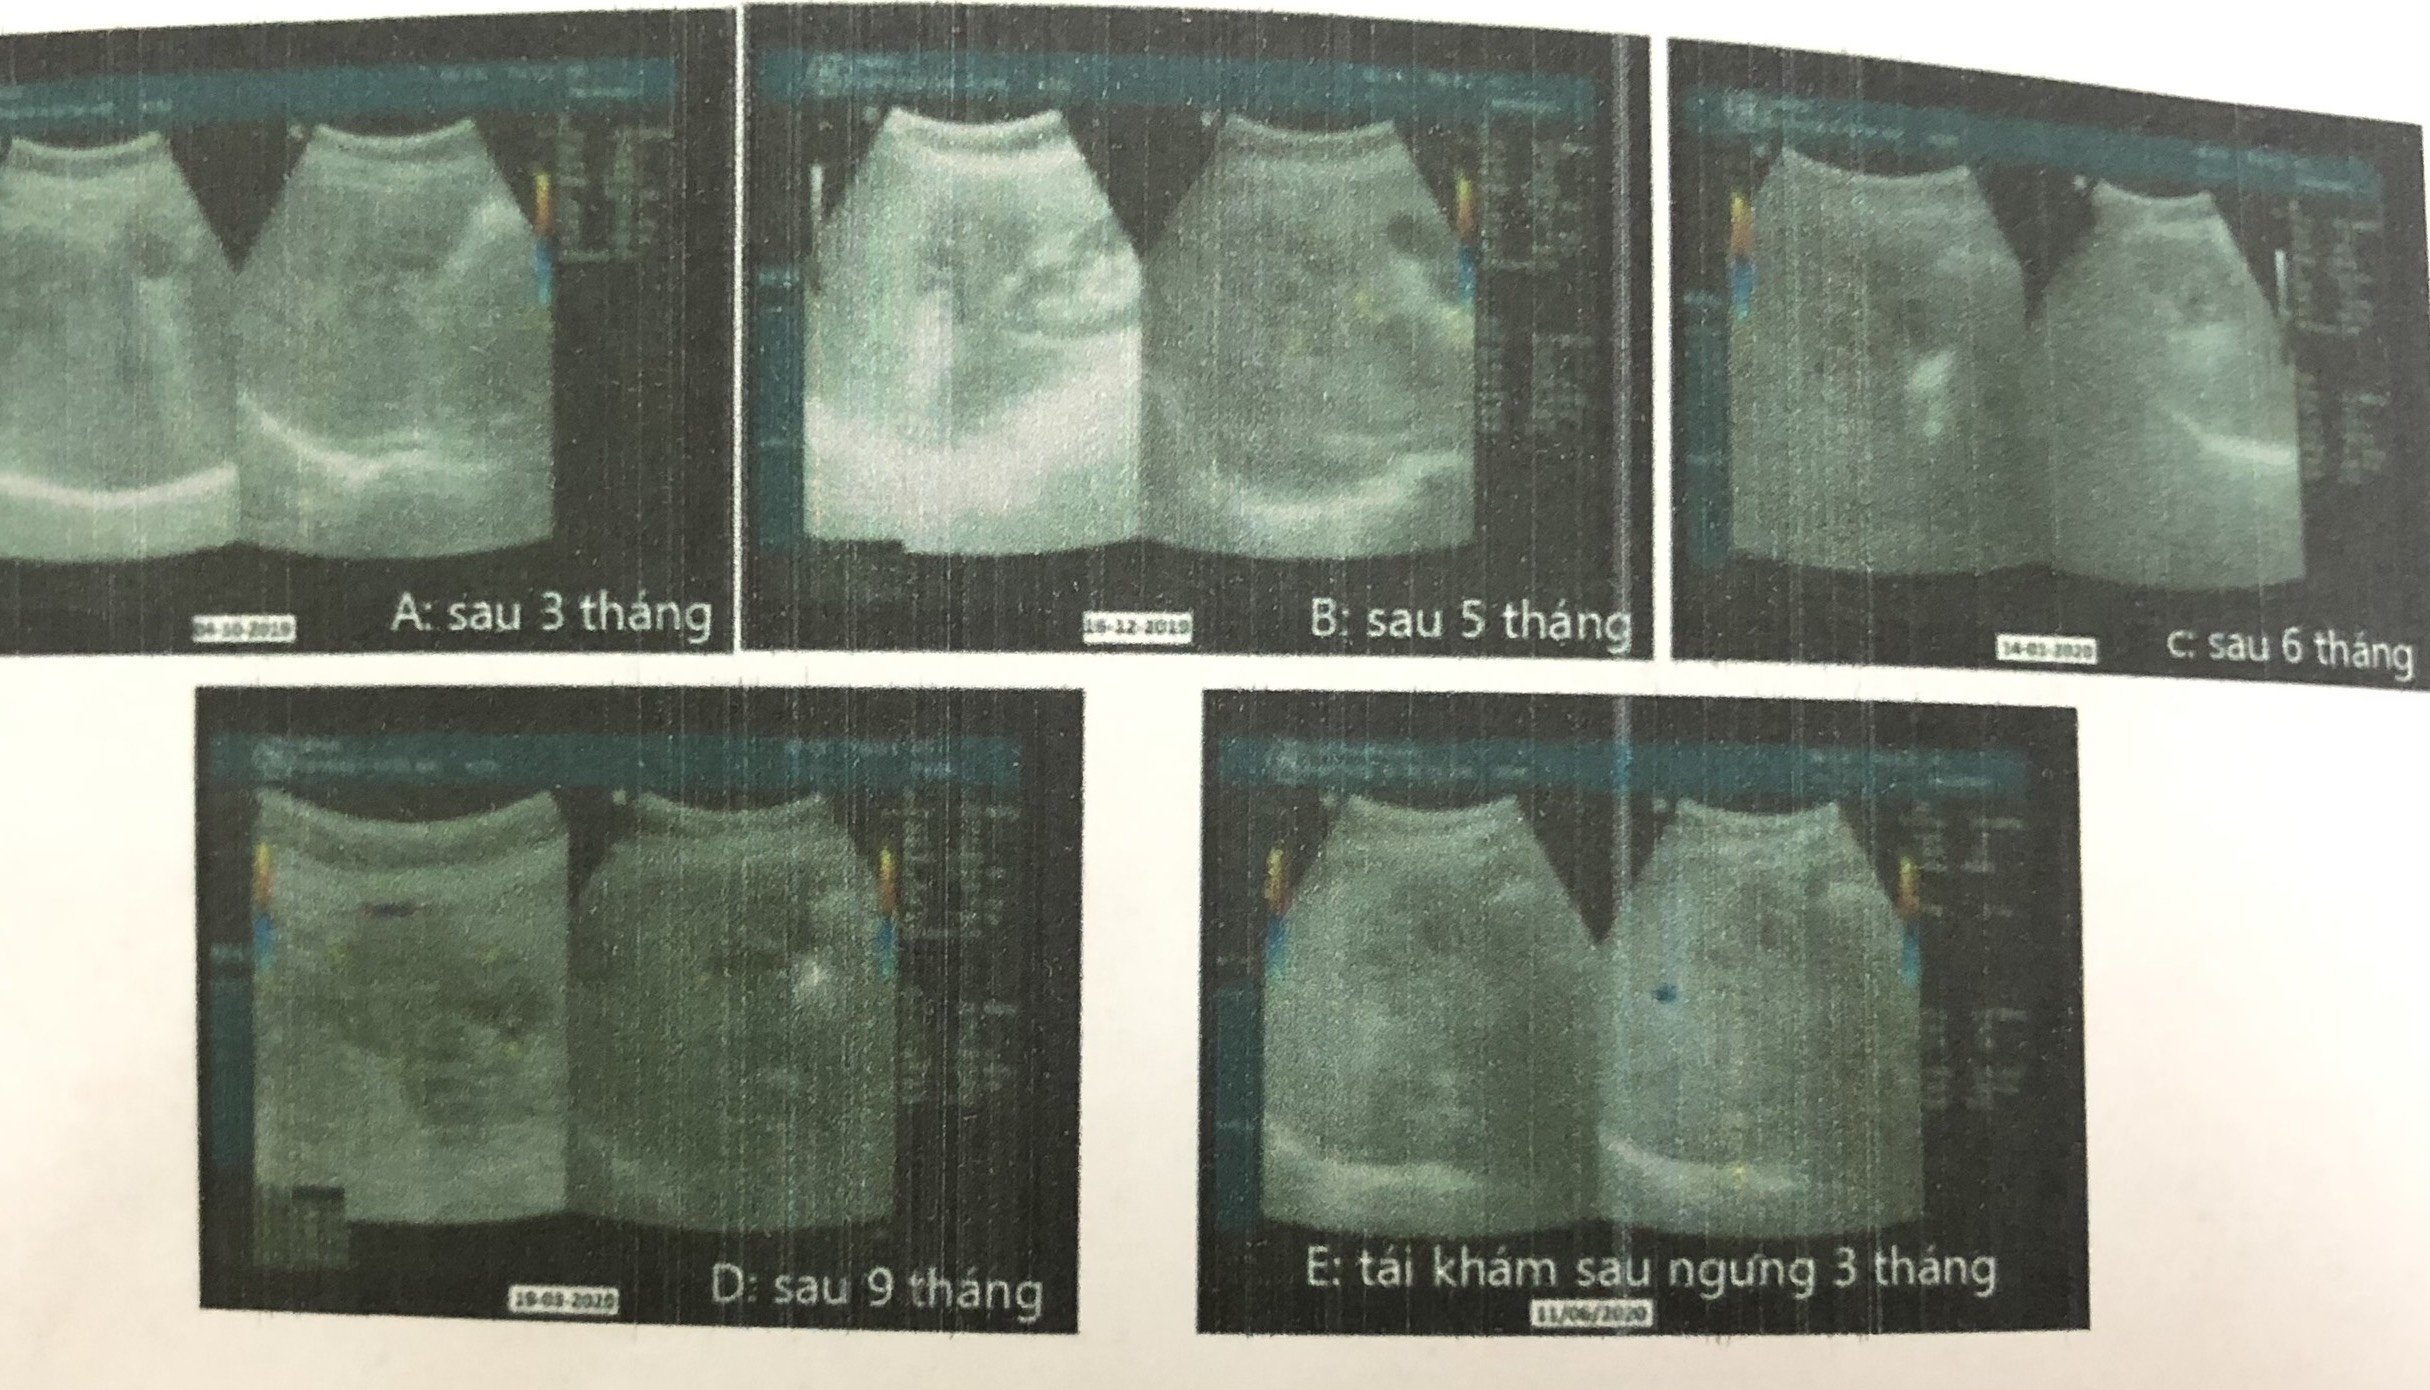

Diễn biến điều trị trên phim siêu âm của bệnh nhân. Ảnh: BVCC.

Sau một tháng điều trị theo phác đồ, bệnh nhân dung nạp thuốc tốt, khỏi hoàn toàn triệu chứng lâm sàng. Sau 9 tháng dùng thuốc chống lao, bệnh nhân bình phục, không ghi nhận biến chứng bất lợi.